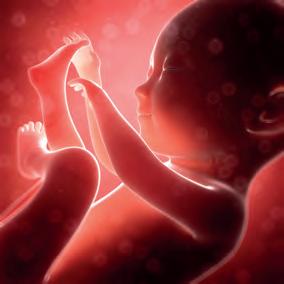

De spermacel uit de stuifmeelkorrel versmelt met één eicel in het zaadbeginsel. Hierbij versmelt het erfelijk materiaal. Dat is de bevruchting. De bevruchte eicellen groeien hierna uit tot embryo’s.

Uit de stuifmeelkorrel op de stempel groeit een stuifmeelbuis richting zaadbeginsel. De bevruchting gebeurt wanneer de spermacel uit de stuifmeelkorrel versmelt met de eicel in het zaadbeginsel. Er ontstaat een bevruchte eicel die uitgroeit tot een embryo.

Bij gunstige omstandigheden groeit een zaad uit tot kiemplant. Tijdens de kieming haalt het embryo zijn voeding uit de zaadlobben. Eerst groeit de wortel en dan de stengel.